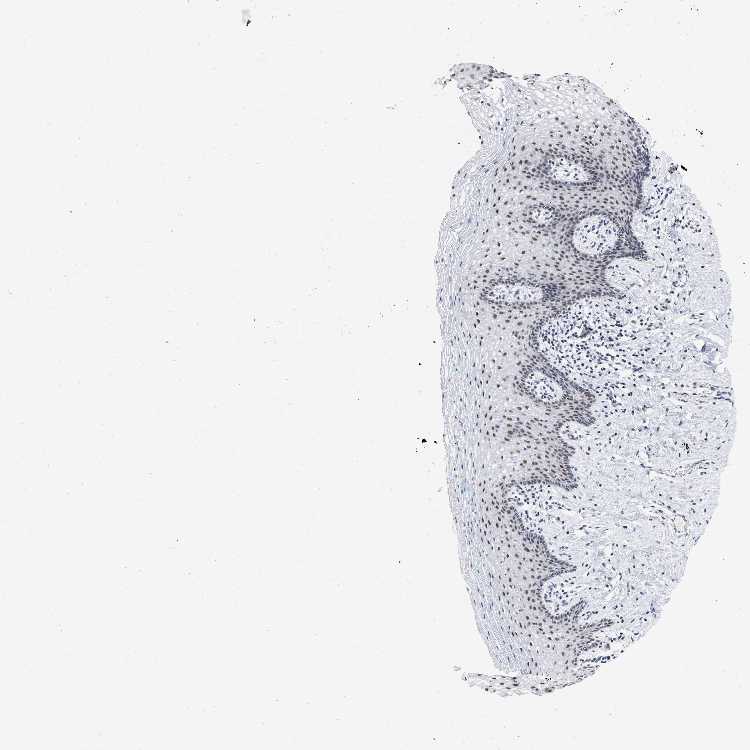

TISSUE PRIMARY DATA VAGINA Show tissue menu

VAGINA - Antibody stainingi

Antibody staining in the annotated cell types in the current human tissue is reported as not detected, low, medium, or high, based on conventional immunohistochemistry profiling in selected tissues. This score is based on the combination of the staining intensity and fraction of stained cells.

Each image is clickable and will lead to virtual microscopy that enables deeper exploration of all samples and also displays staining intensity scores, fraction scores and subcellular localization as well as patient and tissue information for each sample.

Antibody HPA017911Antibody HPA048803

Squamous epithelial cells MediumMedium